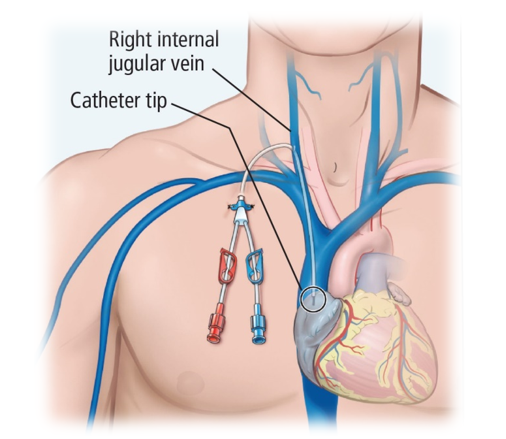

– Acesso venoso periférico e central (em ambiente hospitalar)

FONTE: Cleveland Clinic Journal of Medicine.